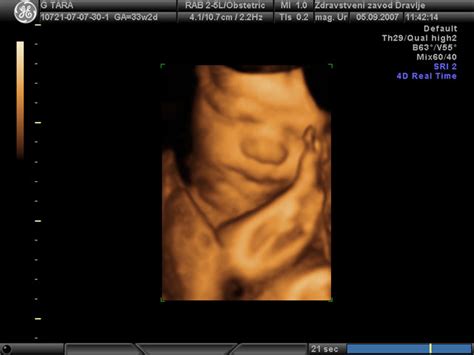

3D/4D Ultrazvok: Čustvena povezava in podrobnejša diagnostika

Novejša tehnologija 3D/4D ultrazvoka omogoča staršem vpogled v fotografsko realistično tridimenzionalno sliko otroka v maternici ter celo video posnetke, v katerih lahko opazujejo njegovo premikanje. Ta preiskava, ki je še posebej čudovita med 18. in 32. tednom nosečnosti (idealno med 26. in 28. tednom), ne le krepi čustveno navezanost staršev na plod, temveč lahko zdravnikom pomaga pri natančnejšem ocenjevanju razvoja ploda, vključno z obraznimi in drugimi nepravilnostmi. Omogoča opazovanje vedenjskih vzorcev ploda, kot so premikanje, smejanje, zehanje ali sesanje prsta. Čeprav strokovno še ni obvezen del pregleda fetalne morfologije, 3D/4D ultrazvok izboljšuje odkrivanje nekaterih razvojnih nepravilnosti in omogoča bolj natančen pregled notranjih organov.